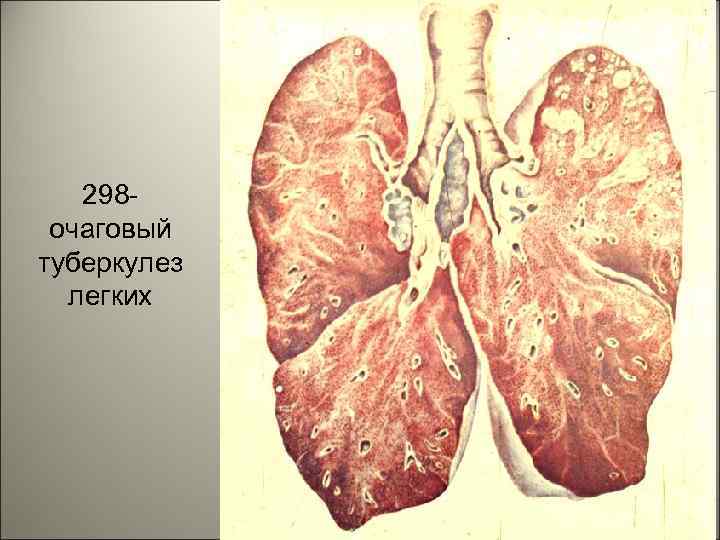

298 очаговый туберкулез легких 37